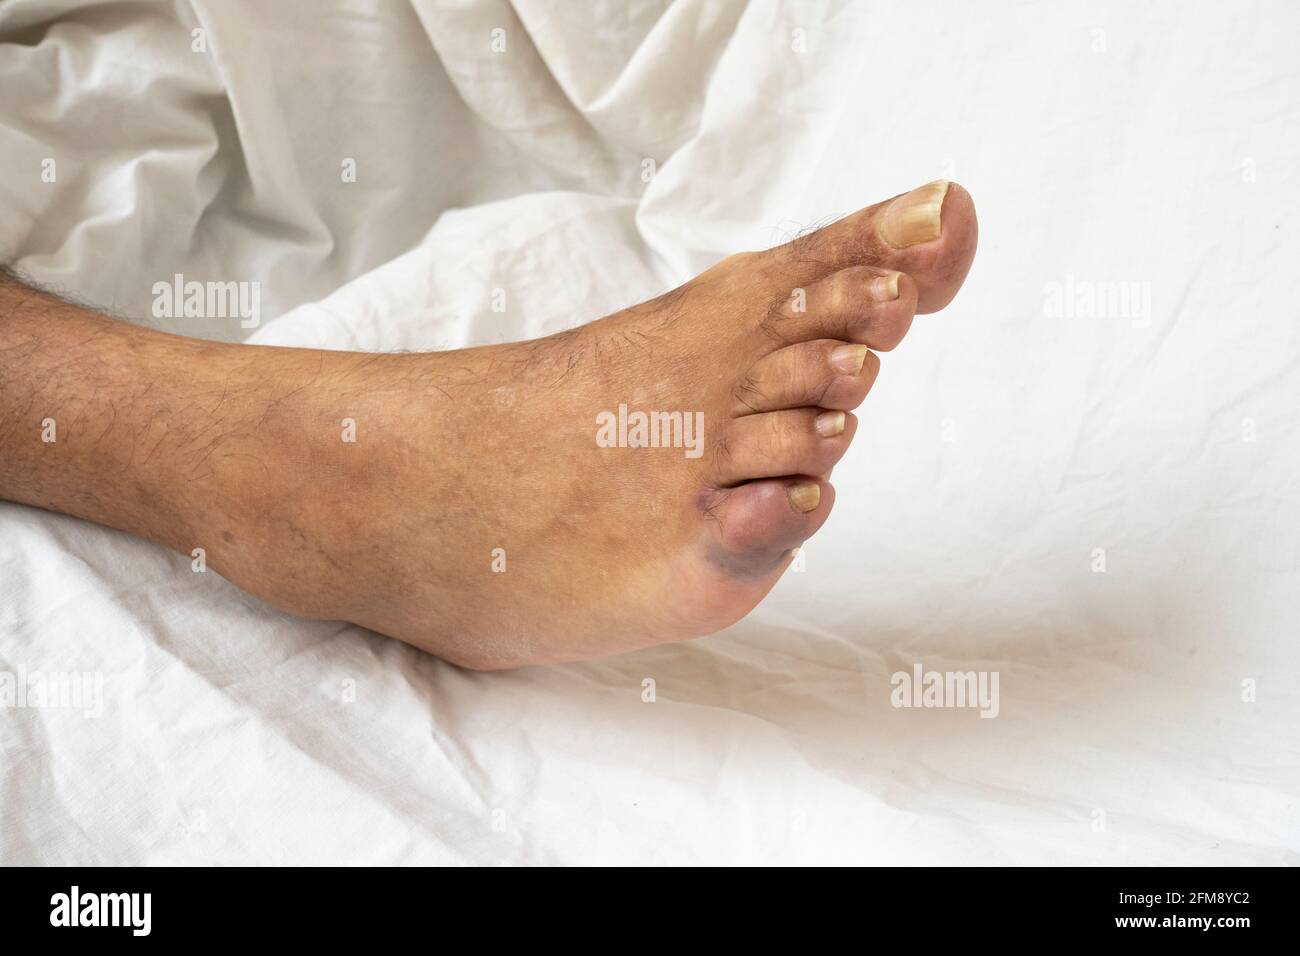

RF2FM8YC2–Blutergüsse an der kleinen Fußspitze. Nahaufnahme der gebrochenen kleinen Zehe eines älteren Mannes, der Verfärbungen zeigt.